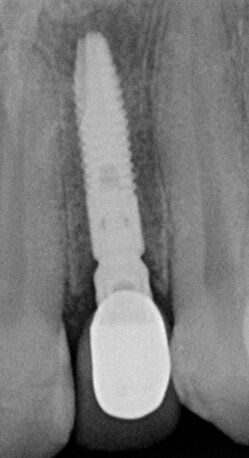

Fig. 4b - Rx endorale post-operatoria impianto sede 22.

Fig. 6b - Controllo radiografico a un mese.